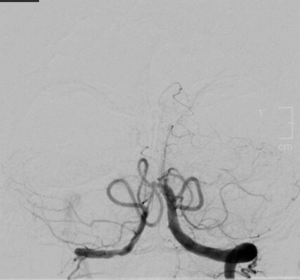

As with other ischemic changes, non-contrast head CT and CT angiography (CTA) are included in the initial workup of BAO. Vascular imaging (e.g., CTA) is a more sensitive method for determining the degree of stenosis and infarction in BAO. Diffuse weighted imaging (DWI) sequences in magnetic resonance imaging (MRI) of the head can demonstrate acute ischemic infarct. CT or MRI of the neck with CTA or MRA of the neck can demonstrate the occlusion as well as more proximal disease in BAO (e.g., vertebral artery dissection). Although CTA and MRA are often diagnostic in BAO, catheter digital subtraction angiography may be necessary in some cases.[3]